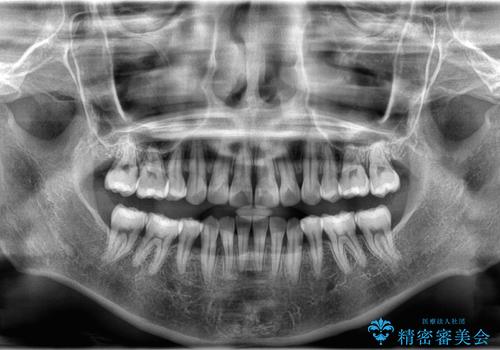

- 前歯が出ていることと、下の歯のがたがたで歯磨きがしにくいことを主訴に来院されました。

マウスピース矯正の希望があり、ワイヤーリカバリの可能性を伝えたうえでインビザライン抜歯矯正を行っています。

来院が途中途絶えたこともあり、4年ぐらい期間がかかりましたが、インビザラインだけで治療を終えることができました。